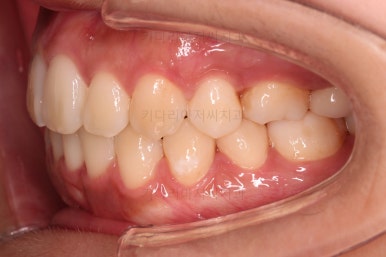

중앙선, 교합, 앞니 맞물림 등 모든 것이 좋아졌네요.

교합, 정중선 모두 좋아졌고요.

입도 약간 더 들어가면서 예쁜 옆라인이 되었네요.

웃을 때 한 쪽으로 쏠려있던 중앙도 개선되어 예뻐졌고, 치아 높낮이도 조절하여 웃을 때 보이는 앞니의 길이도 매우 예븐 정도로 조절이 되었습니다.